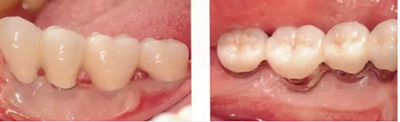

▲圖8-5,6

圖8-5 佩戴上部基臺時的(牙合)面照。獲得了充足的角化齦。

圖8-6 佩戴最終修復體時的(牙合)面照。

▲圖10-9,10

頰舌側都獲得了充足的角化齦,菌斑控制狀態(tài)良好。

▲圖10-11,12

佩戴最終修復體后2年的狀態(tài)。頰舌側角化齦寬度均充足。